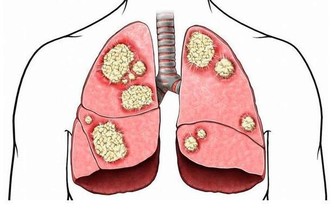

負擔過重、行動姿勢不當、寒氣侵入等都會讓腿腳受傷。另外,腿腳最容易受到傷害的地方是關節。